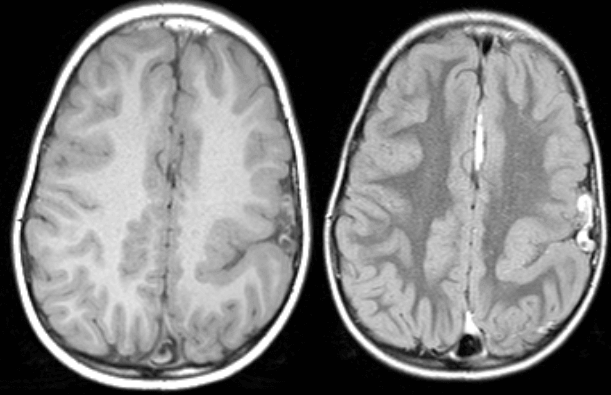

Schizencephaly is a developmental abnormality in brain structure consisting of a cleft from the pia into brain parenchyma, lined by heterotopic gray matter.

Clefts that connect with the lateral ventricle are “open lip” schizencephaly and clefts that do not connect with the ventricle (like that shown in the image above) are closed lip.

The clefts are often non-functional, causing paralysis if they are in a motor area.

Seizures are common in these patients. The abnormal sulcus can produce a horizontal dipole on EEG, sometimes causing difficulty in localizing a seizure locus.